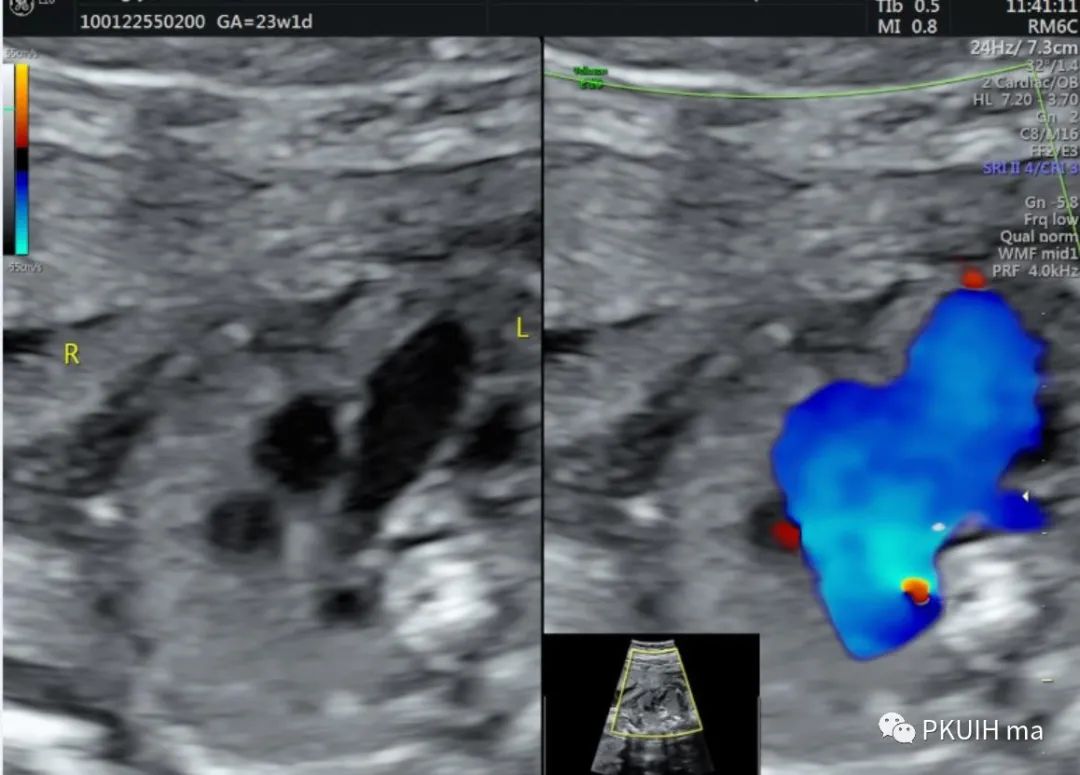

下面几张图都是右位主动脉弓、左动脉导管合并左锁骨下动脉迷走的病例,患儿出生后随访均无明显临床症状

主动脉弓走行于气管的右侧,与左位的动脉导管形成“U”型环(不完全血管环),包绕气管和食管。主动脉冠状切面可见左锁骨下动脉起自于主动脉弓降部,向左肩部走行。

右弓左导管是左位主动脉弓在左锁骨下动脉与左颈总动脉起始处之间退化,形成右弓,左位动脉导管存在于左锁骨下起源区域,右位动脉导管退化,从而形成左向右环绕气管的血管环。右位主动脉弓依次发出左颈总动脉、右颈总动脉、右锁骨下动脉及迷走的左锁骨下动脉。在个别情况下,左锁骨下动脉也可以通过Kommerell憩室的动脉管道直接起源于降主动脉。右位主动脉弓可以是复杂先心的一部分,也可以孤立存在。三血管气管切面是诊断右位主动脉弓的重要切面,结合血流显像可以鉴别右弓的三种类型。